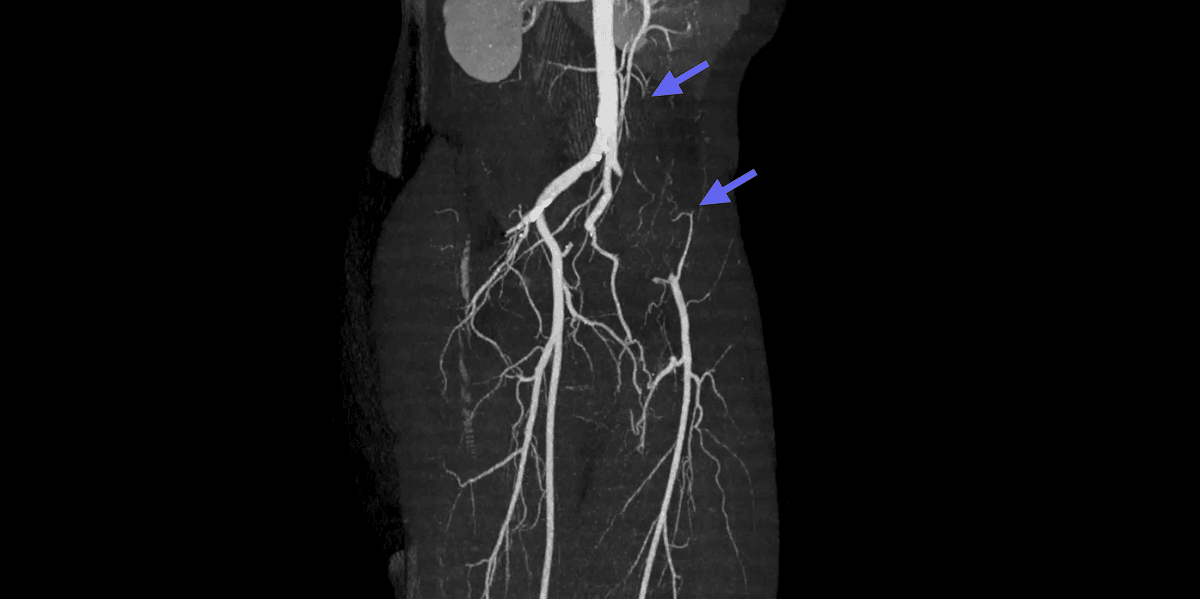

Endofibrose de l'artère iliaque externe

L'endofibrose de l'artère iliaque externe est une pathologie vasculaire rare qui affecte les athlètes d'endurance de haut niveau, en particulier les cyclistes.